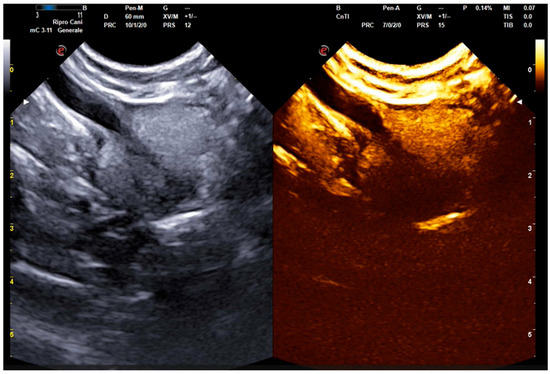

2.2. B-Mode and Contrast-Enhanced Ultrasound Procedures

- Russo, M.; Vignoli, M.; England, G.C.W. B-mode and contrast-enhanced ultrasonographic findings in canine prostatic disorders. Reprod. Domest. Anim. 2012, 47, 238–242. [Google Scholar] [CrossRef] [PubMed]

- Troisi, A.; Orlandi, R.; Bargellini, P.; Menchetti, L.; Borges, P.; Zelli, R.; Polisca, A. Contrast-enhanced ultrasonographic characteristics of the diseased canine prostate gland. Theriogenology 2015, 84, 1423–1430. [Google Scholar] [CrossRef] [PubMed]

- Russo, M.; Vignoli, M.; Catone, G.; Rossi, F.; Attanasi, G.; England, G.C. Prostatic perfusion in the dog using contrast-enhanced Doppler ultrasound. Reprod. Domest. Anim. 2009, 44, 334–335. [Google Scholar] [CrossRef]

- Bigliardi, E.; Ferrari, L. Contrast-enhanced ultrasound of the normal canine prostate gland. Vet. Radiol. Ultrasound 2011, 52, 107–110. [Google Scholar] [CrossRef]

- Vignoli, M.; Russo, M.; Catone, G.; Rossi, F.; Attanasi, G.; Terragni, R.; Saunders, J.; England, G.C. Assessment of vascular perfusion kinetics using contrast-enhanced ultrasound for the diagnosis of prostatic disease in dogs. Reprod. Domest. Anim. 2011, 46, 209–213. [Google Scholar] [CrossRef] [PubMed]

| Wash-in (s) | 11.93 ± 2.08 (8–16) | 14.73 ± 2.54 (10–21) | <0.001 |

| Wash-out (s) | 42.20 ± 6.99 (35–60) | 51.13 ± 6.03 (46–65) | <0.001 |